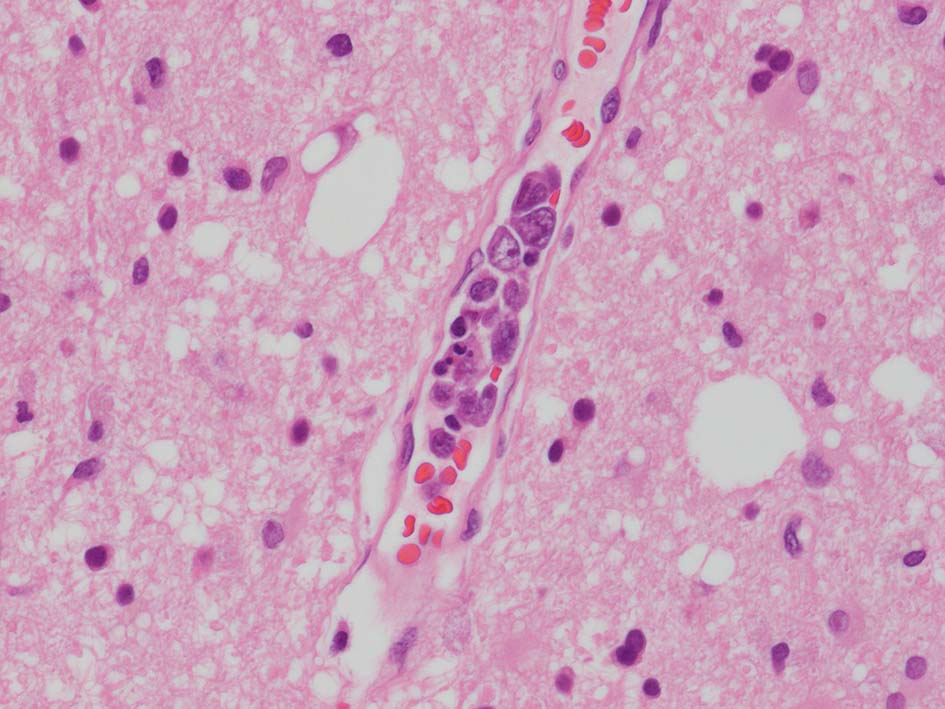

脳;くも膜下腔の小動脈内, 脳白質の細血管内に腫瘍細胞が充満している。